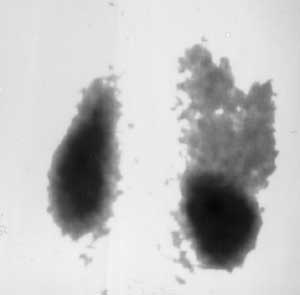

Рис. 3. Сцинтиграфия опухолей забрюшинного пространства. Определяется смещение правой почки книзу опухолью надпочечника.